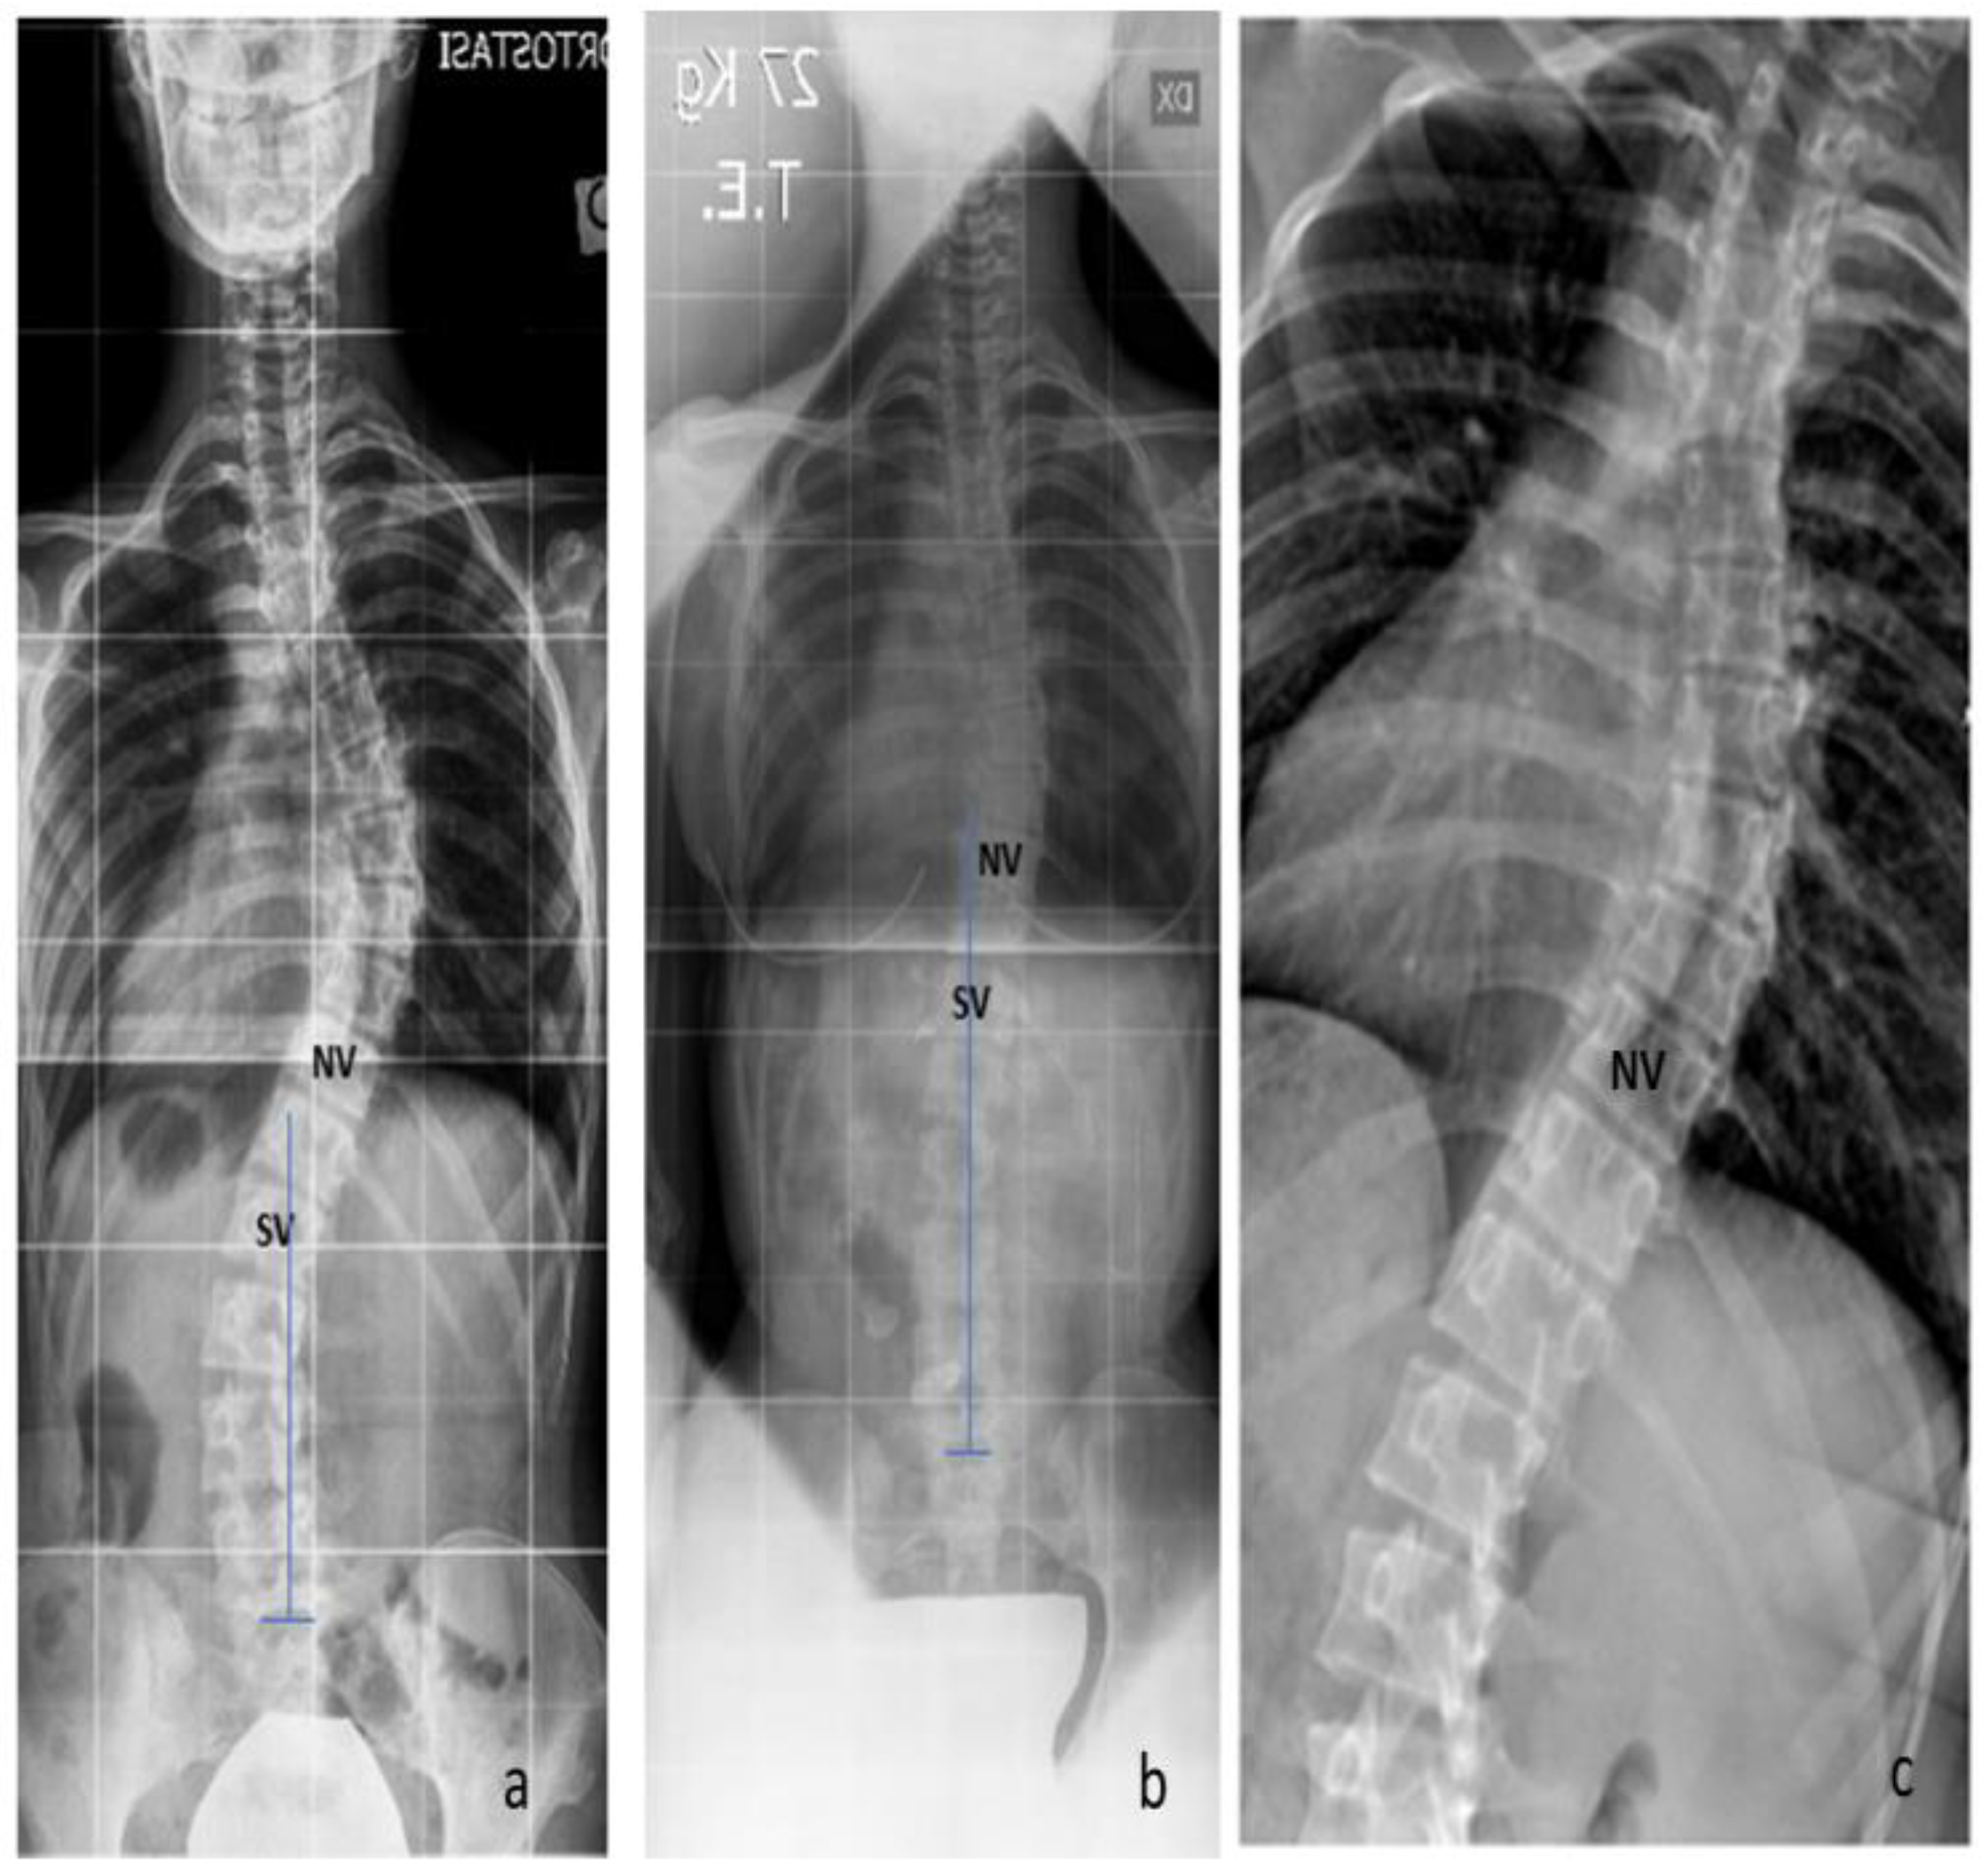

A comparison between the TR and preop X-rays was conducted concerning the gravitational stability of the curve, while the rotational stability was evaluated on the TR, SB, and preop X-rays. The gravitational stability was assessed by evaluating the SV, while the rotational stability was assessed by evaluating the NV. Regarding the gravitational stability, in 23 cases (54.8%), we observed a proximalization of the SV at the TR with respect to the preop X-rays (Figure 2; mean + 2.4 ± 1.2 levels); in 11 cases, we observed no modification of the SV; while in 8 cases, the SV-TE was more distal than the SV-preop. The ‘distalization’ of the SV-TR was observed only in the Lenke 1C curves, (8 out of 16 cases). In those cases with distalization of SV, a significantly greater correction of the Cobb angle of the distal curve was observed both with SB and TR (SB: 62.2 ± 8.8% vs. 49.5 ± 12.9%, p = 0.05, t-test; TR 60.1 ± 6.5% vs. 44.6 ± 10.7%, p = 0.05, t-test) (Figure 3).

Figure 2. Gravitational stability: the proximalization of the SV at the TR with respect to the preop X-rays. (a) The SV-preop is L1; (b) the SV-TR is T12; (c) the SB shows the proximalization of the NV.